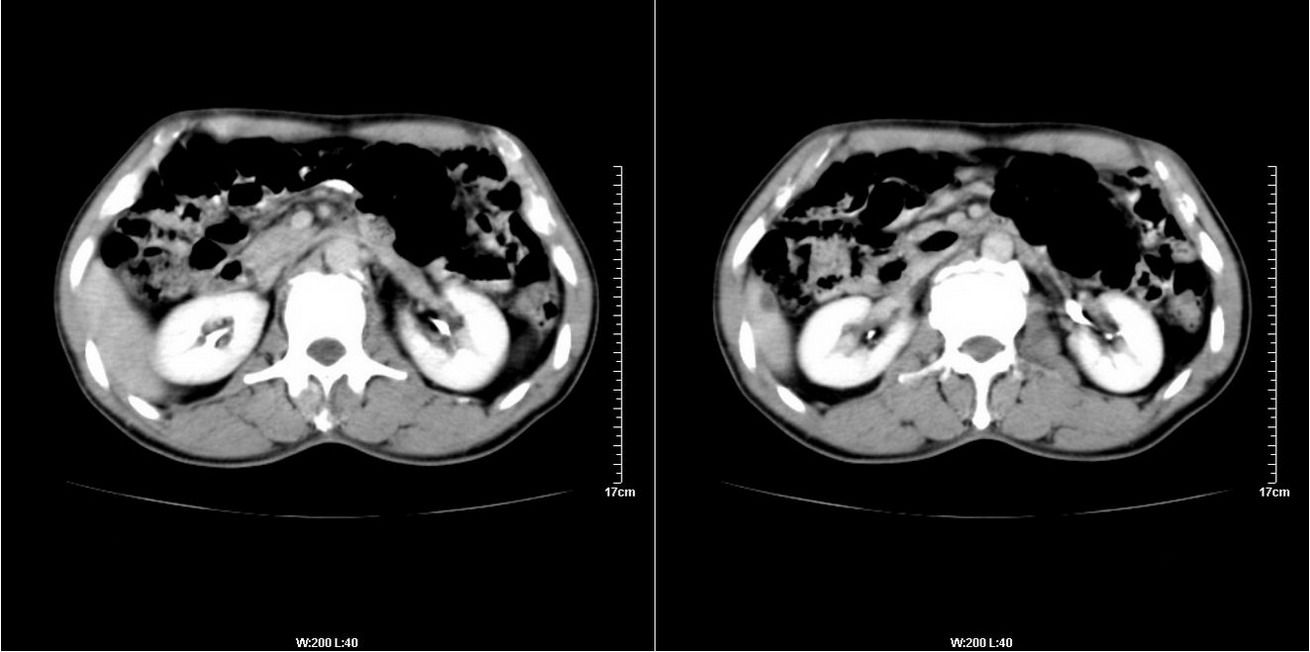

标题: CT14220:男性,59岁。腹部疼痛不适半年余。 [打印本页]

标题: CT14220:男性,59岁。腹部疼痛不适半年余。

上腹部实质性脏器未见明确异常

上腹部未见明显异常改变